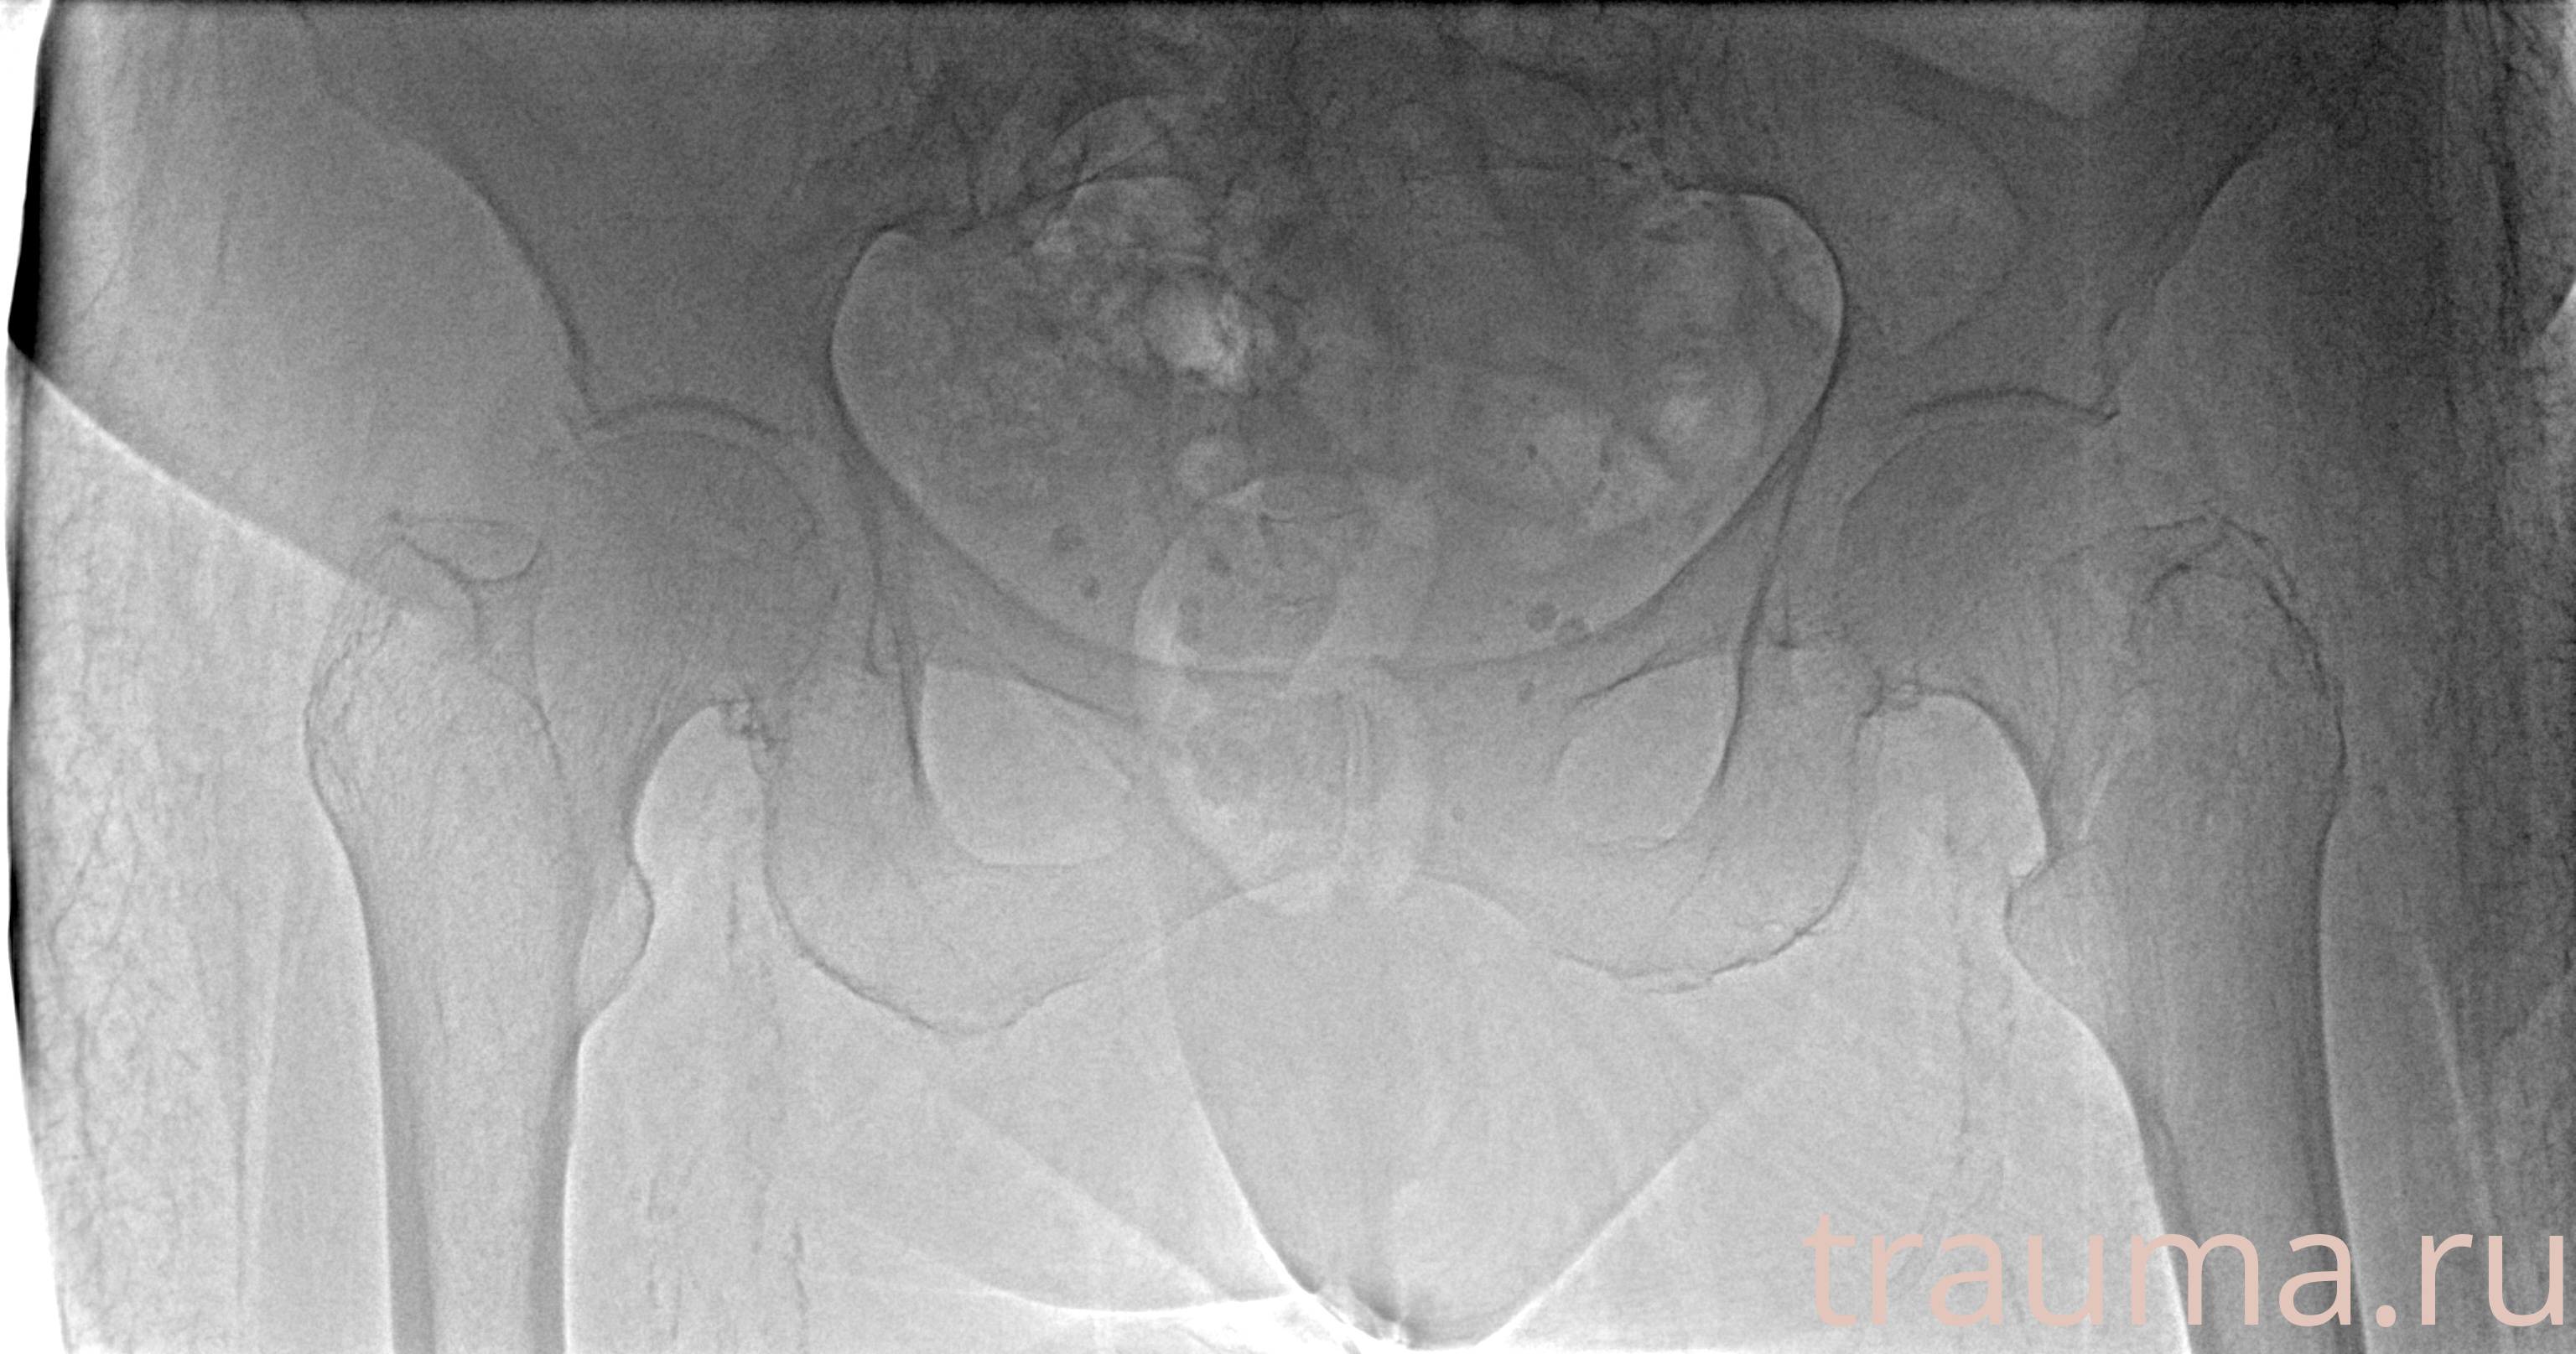

Рентген на дому: по вашему адресу приезжает врач-рентгенолог, травматолог-ортопед с мобильным рентгеновским аппаратом, проводит диагностику травмы или заболевания, делает необходимые рентгенограммы, дает рекомендации по дальнейшему лечению. Получить качественные снимки в домашних условиях возможно благодаря уникальной методике, разработанной МосРентген Центром для института  Склифосовского

при переломе шейки бедра и пневмонии от компании МосРентген Центр - партнера Института имени Склифосовского